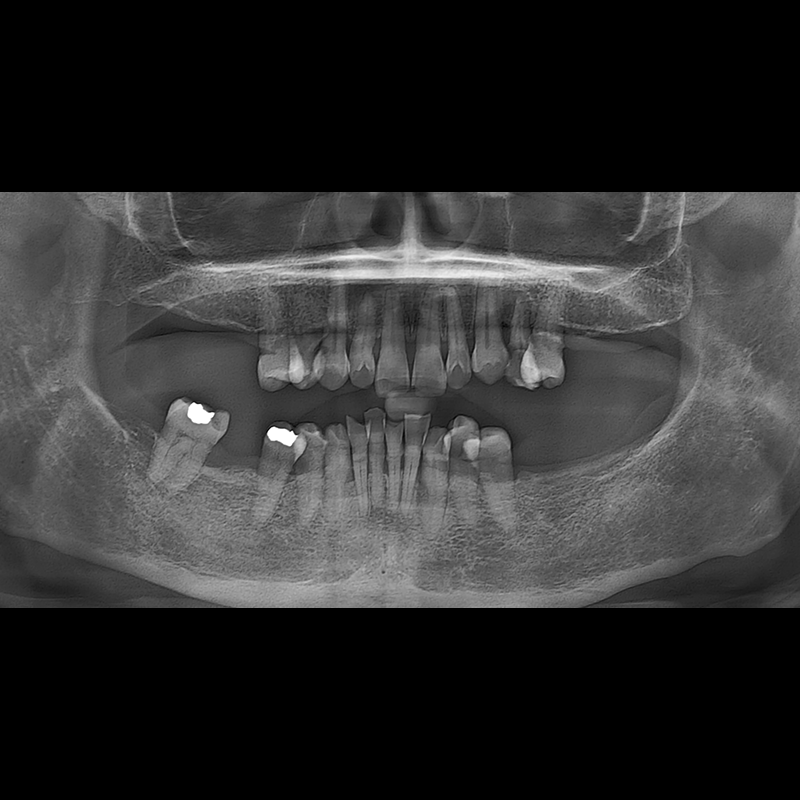

IMPLANT

BEFORE AFTER

インプラント手術事例 2025.05.30

欠損した歯の部分と、生かしにくい歯の位置にインプラントを植立しました。